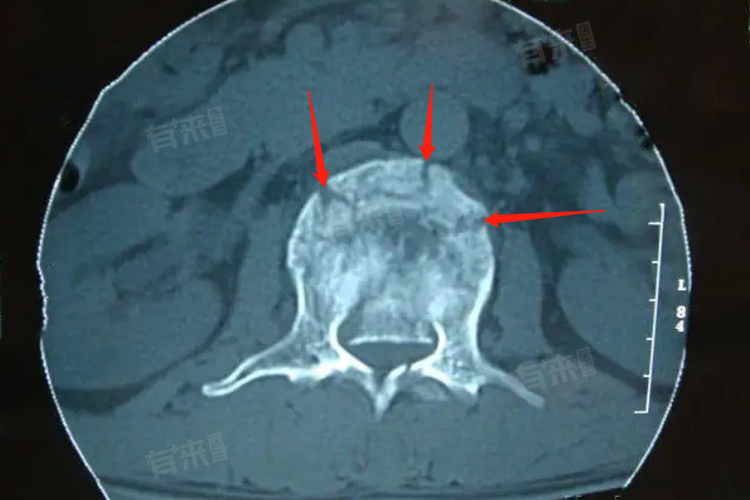

- 腰椎骨裂指的是腰椎部分区域出现裂缝或断裂,这种情况可能是由于突然的剧烈运动、跌倒、交通事故或者长期的过度使用造成的。年轻患者通常拥有较好的骨骼质量和更快的新陈代谢速度,因此他们的恢复过程可能会比年长者来得更快一些。然而,即使是年轻人,如果存在营养不良或者其他健康问题,也可能延长恢复期。

对于那些骨折较为严重或伴有其他并发症(如神经压迫)的患者,则可能需要考虑手术干预。手术的目的通常是修复受损的骨骼结构,减轻对周围组织的压力,并为后续的康复创造条件。术后恢复同样需要一段时间,患者需严格遵守医嘱,参加专业的康复训练计划,以促进身体尽快复原。